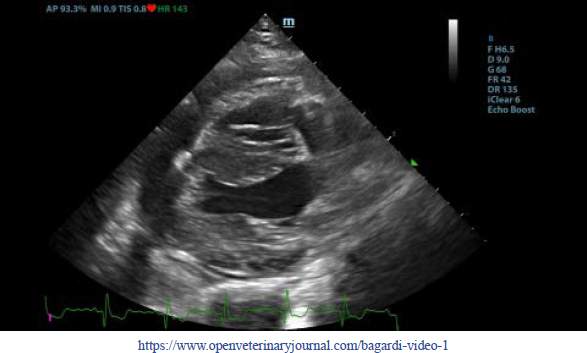

First, transthoracic echocardiogram findings were a small amount of circumferential tamponating pericardial effusion (Fig. 1) and a severe hyperechoic pericardial thickening (10.2 mm) (Fig. 2). The right atrium was normal in size and there was collapse during systole. There was mild septal flattening seen on short axis view of the left ventricle. A short-axis left ventricular M-mode showed posterior displacement of the interventricular septum during late diastole at the time of atrial systole (Fig. 3). The epicardium and pericardium had a hyperechoic appearance with a thin, shaggy layer of heterogeneous echogenic material lining the surface of each (Fig. 1, Supplementary Video I). Pericardiocentesis was not recommended at this time given that the patient was minimally clinically and hemodynamically affected. Few hours later, a second echocardiographic examination, after stabilization of left ventricular volume with intravenous (IV) lactate ringer solution at maintenance rate, showed a worsening of pericardial thickness (13 mm) and an increase in pleural effusion. Furthermore, there was a >25% mitral inflow variation noted with respiration. In addition, there was >30% tricuspid inflow variation with respiration, signs of CP. During the second echocardiography, the patient appeared to be slightly dyspneic due to the increased thoracic effusion.

Fig. 1. Transthoracic echocardiogram – right parasternal long-axis four-chambered view. Note the pericardial effusion, the right atrial collapse (white arrow), the thickened, hyperechoic pericardium, and the scant pericardial effusion (white arrowhead). LA: left atrium; LV: left ventricle; RA: right atrium; and RV: right ventricle.

Supplementary Video I. Transthoracic echocardiogram – right parasternal long-axis four-chambered view. Note the thickened, hyperechoic pericardium, the pericardial effusion, and the hyperechoic appearance of the epicardium and pericardium with a thin, shaggy layer of heterogeneous echogenic material lining the surface of both. The left ventricular chamber appears empty, and the walls are pseudohypertrophic.